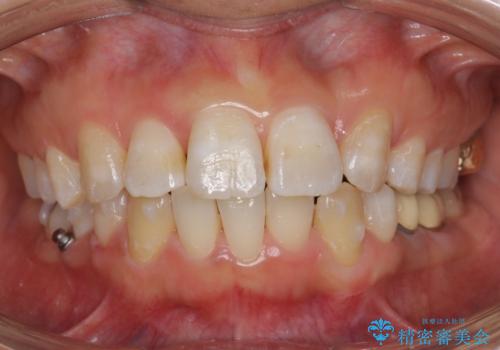

歯のがたつき インビザラインで矯正

- 歯並びを主訴に来院。

左上2番は以前抜歯したとのこと。

奥歯を後ろに下げて、前歯を並べています。

マウスピースと矯正用のミニスクリューを使用して治療しています。